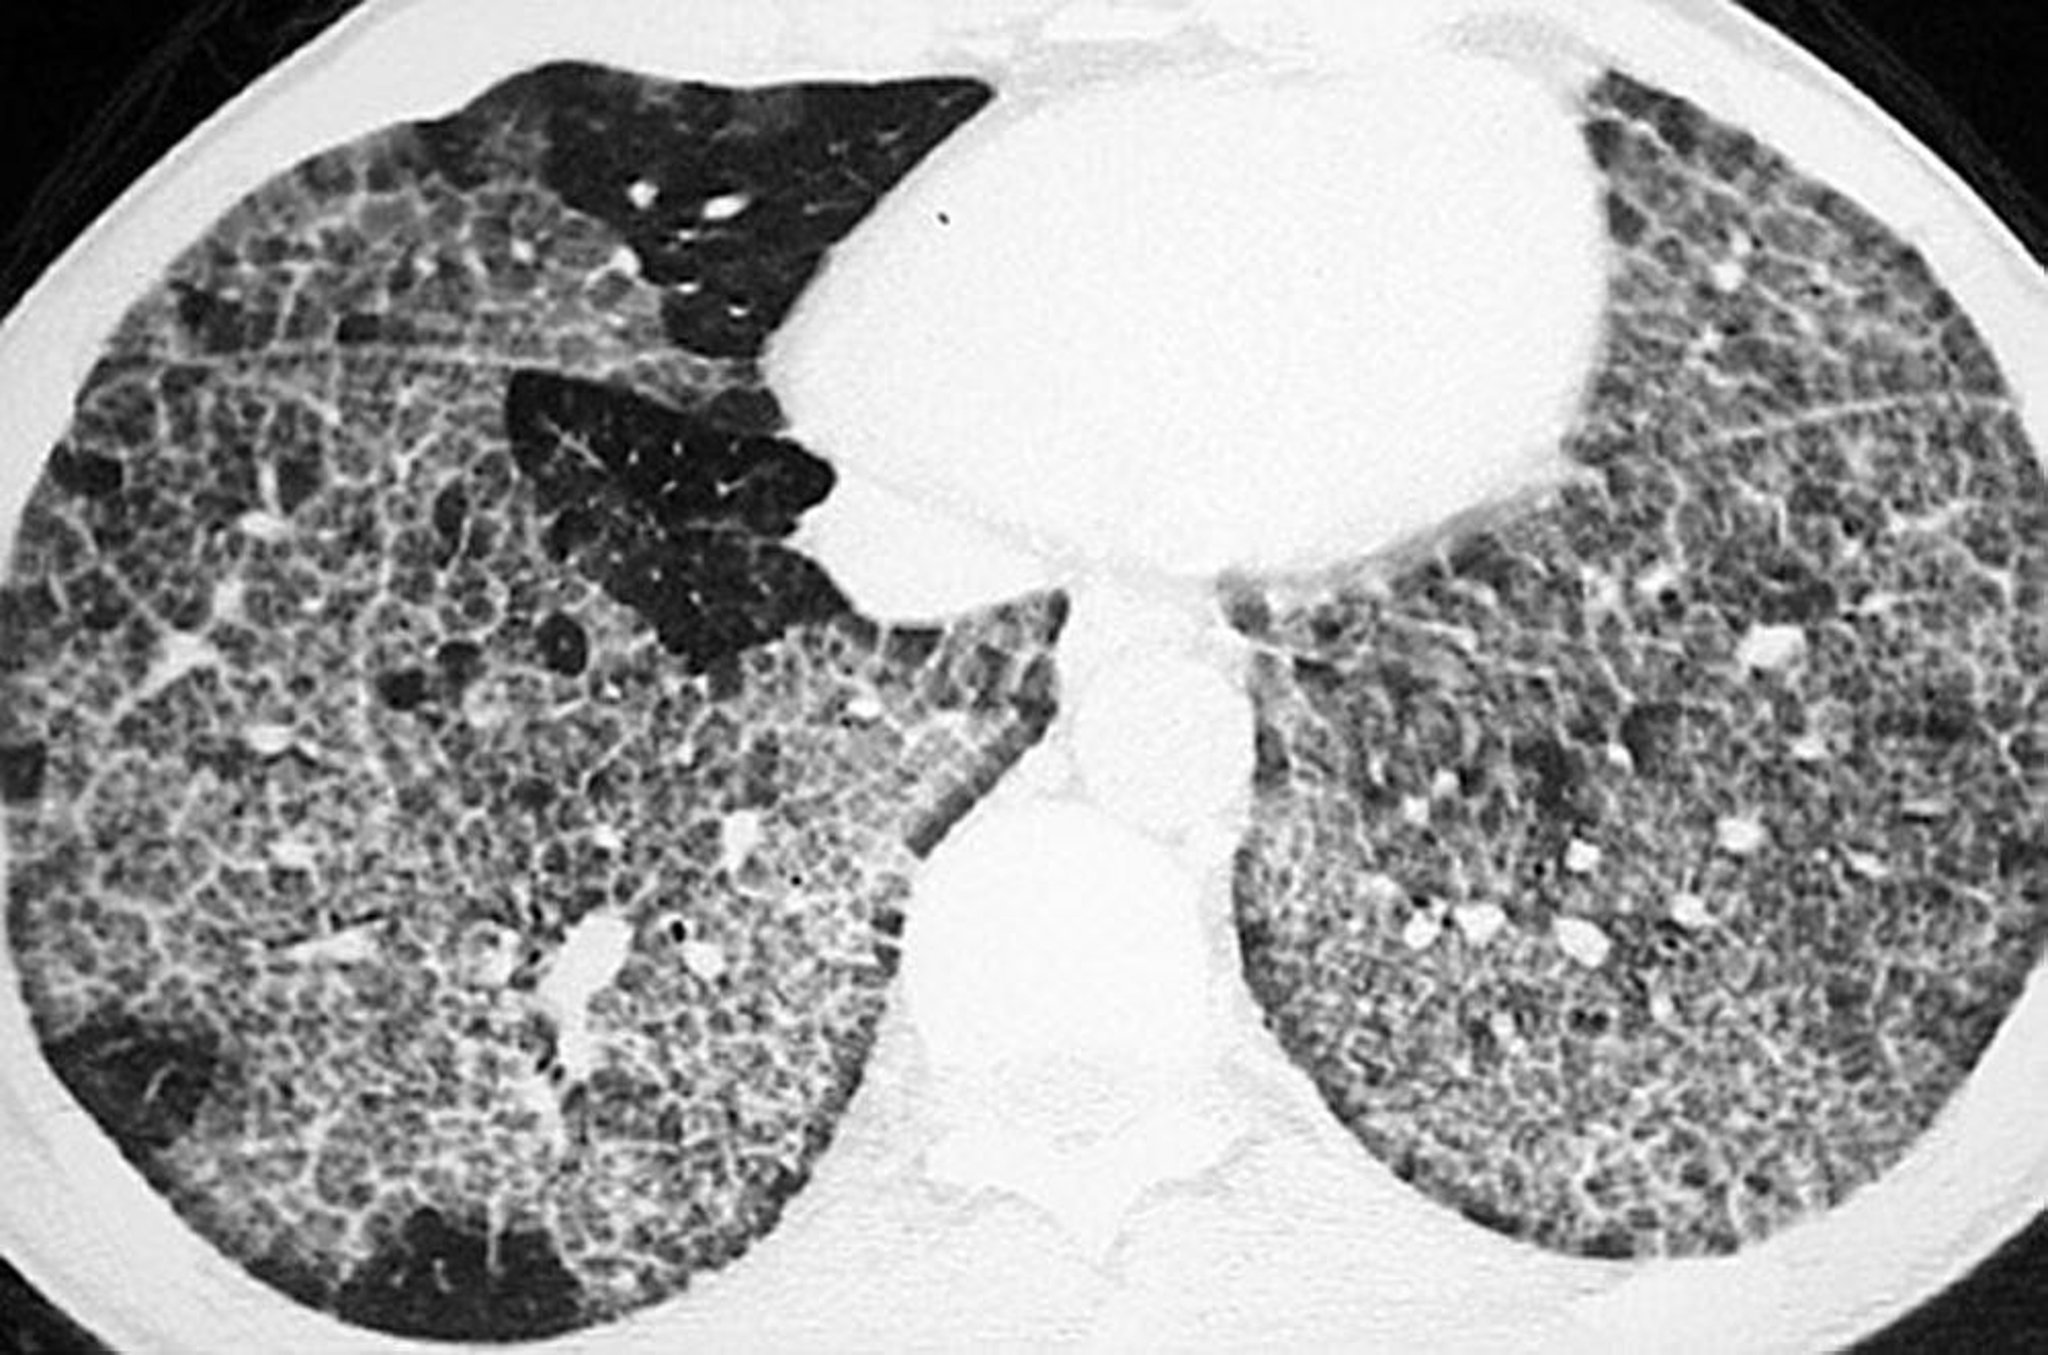

Легеневий альвеолярний протеїноз (КТ сканування)

High-resolution CT shows ground-glass opacification and thickened intralobular structures and septa in polygonal shapes ("crazy-paving").

Image courtesy of Talmadge E. King, MD.